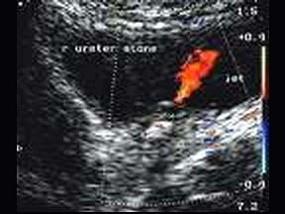

图中所示为?(?)A.输尿管喷尿征B.膀胱裂C.膀胱占位D.膀胱憩室E.以上都不是

问题 图中所示为?(?)

选项 A.输尿管喷尿征 B.膀胱裂 C.膀胱占位 D.膀胱憩室 E.以上都不是

答案 A